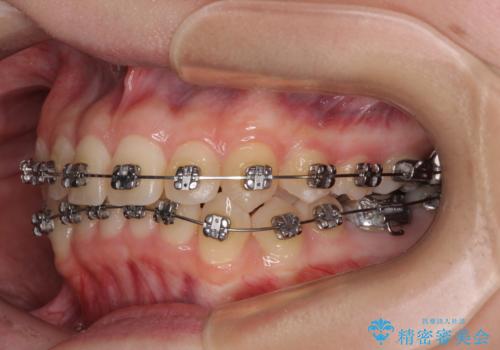

前歯のクロスバイト ギラギラのワイヤー装置で矯正治療

- 矯正装置

- メタルブラケット

- 前歯のクロスバイトを改善したいとのことで来院された患者様です。

マウスピース矯正では前歯の神経への負担が大きいことを懸念され、ワイヤー装置による矯正治療を行うこととしました。

クロスバイトが改善する際は、前歯しか接触しないため、痛みがあったり食事が取りにくかったりと、不便な時期がありますが、1年強の短期間で無事に治療を終えることができました。